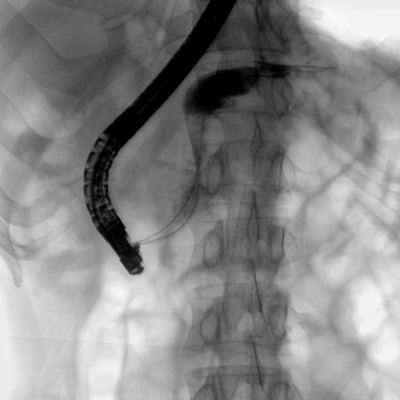

消化內(nèi)科: ERCP、PTCD、肝臟介入(TACE、灌注)、食管支架等。

骨科: 經(jīng)皮錐體成形術(shù)、經(jīng)皮椎間盤臭氧治療術(shù)、胸脊椎固定、骨活檢、腰椎內(nèi)固定術(shù)等。